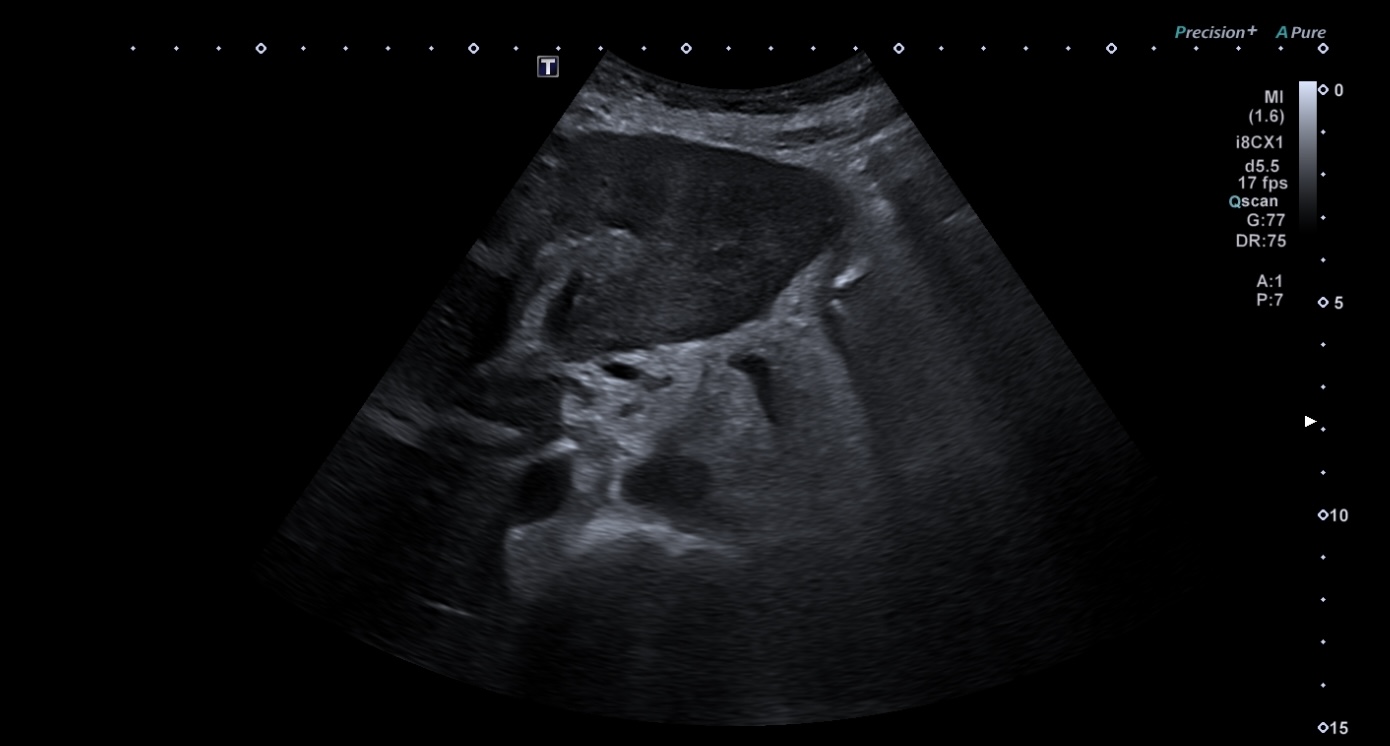

Ecografía abdominal en AP: se observan múltiples LOES hepáticas sugestivas de metástasis.